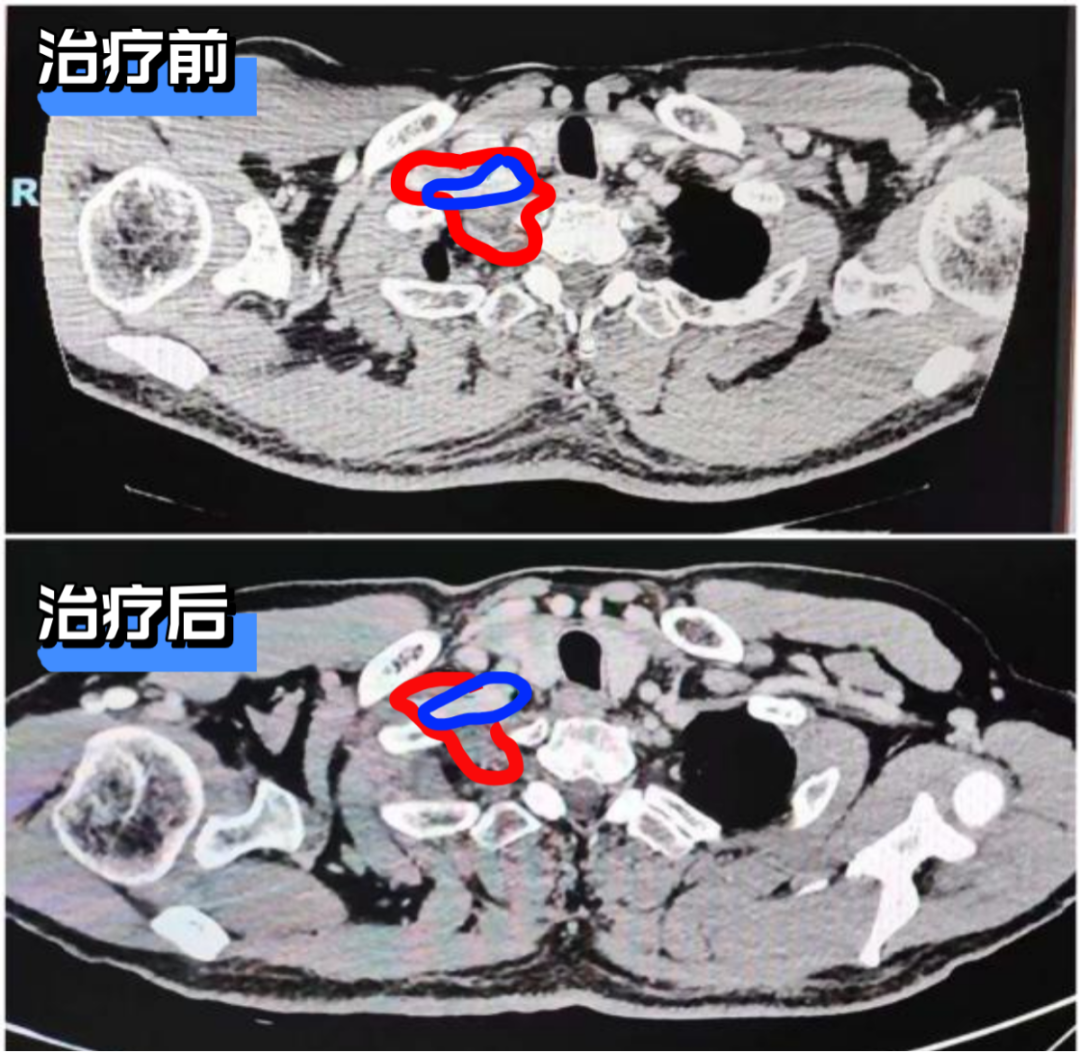

*右锁骨下动脉情况:新辅助治疗前肿瘤侵犯并包绕右锁骨下动脉,动脉壁模糊显示不清。治疗后肿瘤退缩明显,右锁骨下动脉显示清晰。